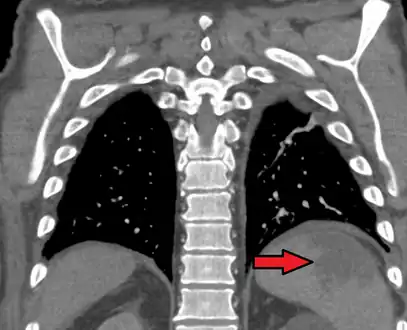

Splenic infarct seen on CT

An abdominal CT scan is the most commonly used modality to confirm the diagnosis,[3] although abdominal ultrasound can also contribute.[16][17][18]